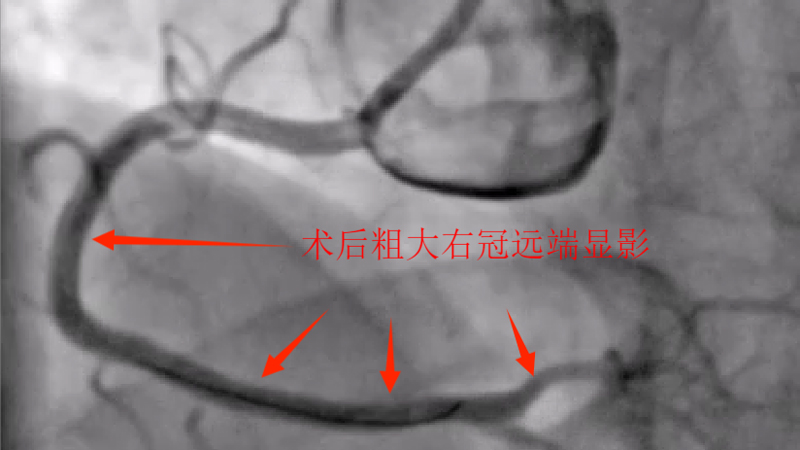

据了解,吴某,男性,58岁,因胸痛就诊,确诊为急性非ST段抬高型心肌梗塞,10多天前有过消化道出血情况,既往有心肌梗塞、痛风、慢性肾功能不全等病史,1年前胃镜提示有胃溃疡病史,口服有多种药物,考虑患者病情危重及复杂,心血管内科介入团队经过讨论后先行冠脉造影后再决定下一步诊疗策略,造影可见:前降支中段发出对角支后极重度狭窄,可见侧支循环右冠中远端,回旋支发出钝缘支后闭塞,可见钝缘支侧支循环回旋支远端;右冠中段闭塞。

经过医护人员精心照顾及治疗,患者各方面情况相对稳定,11月5日心血管内科介入团队再次为患者行冠脉介入治疗。并顺利开通右冠闭塞血管并植入支架恢复正常血流,同期解决前降支极重度狭窄病变并植入支架解除危机。手术总用时1小时40分钟,造影剂用量120ml。